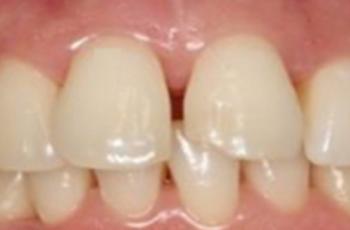

Tratamiento no quirúrgico de la periimplantitis. A propósito de un caso... Cirugía periodontal y periimplantaria | UIC Tratamiento no quirúrgico de la periimplantitis. A propósito de un caso... Se presenta el caso de una paciente de 58 años de edad, sin antecedentes médicos de interés y no fumadora. El motivo... Etiología, diagnóstico y tratamiento de la periimplantitis: Caso... Tto. Periimplantario | UV Etiología, diagnóstico y tratamiento de la periimplantitis: Caso... Presentamos nuevo caso clínico realizado por los doctores Manuel Rodríguez Aranda, Francisco... Efectividad del Tratamiento en Periodontitis Agresiva Tto. Periodontal | UIC Efectividad del Tratamiento en Periodontitis Agresiva El mantenimiento de la dentición natural en estado de salud ha sido un objetivo importante en... Injerto gingival libre alrededor de implantes dentales. A propósito de un... Cirugía periodontal y periimplantaria | UIC Injerto gingival libre alrededor de implantes dentales. A propósito de un... La cirugía mucogingival reconstructiva alrededor de implantes corrige los defectos de la... Terapia mucogingival en implantes: corrección de las secuelas mucosas de... Cirugía periodontal y periimplantaria | UV Terapia mucogingival en implantes: corrección de las secuelas mucosas de... El caso que se presenta a continuación muestra una resolución impecable de un defecto mucogingival... Importancia del mantenimiento en la evolución de un paciente con... Mantenimiento | UV Importancia del mantenimiento en la evolución de un paciente con... La periodontitis agresiva se define como una enfermedad de rápida progresión en la destrucción... Tratamiento de Recesiones Gingivales Clase III de Miller mediante técnica... Cirugía periodontal y periimplantaria | UIC Tratamiento de Recesiones Gingivales Clase III de Miller mediante técnica... El caso clínico que presentamos a continuación es el de una paciente que acude a la consulta... Tratamiento de un paciente con periodontitis crónica moderada generalizada Tto. Periodontal | UIC Tratamiento de un paciente con periodontitis crónica moderada generalizada El caso clínico que se presenta a continuación, muestra el tratamiento de una paciente...